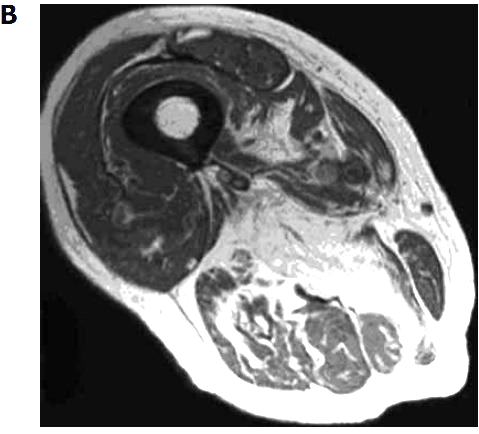

Figure 2

Magnetic resonance imaging of two different grades of fatty degeneration and atrophy involving thigh muscle in patients with vitamin D deficiency.

A Grade 1 (less than 30% of the volume of muscles involved);

B: Grade 2 (30%-60% of the volume of muscles compromised).

For illustration, Figure 2 shows MRI of two different grade of fatty atrophy involving thigh muscle in patients with vitamin D deficiency. The hypothesis that arose was that atrophy of skeletal muscle fibers and their replacement by fat tissue are the anatomic basis for the impairment in muscular performance described in older vitamin D-deficient people[4]. It may supposed that fatty substitution related to vitamin D deficiency may be the result of the lack of the known trophic effects of vitamin D on skeletal muscle cells[4]. If the thigh muscles are affected, the lack of enough muscular bulk may hamper balance and gait. Clinical scores were concordant with this observation. Concerning technical MRI protocols we suppose that a standard, patient-friendly protocol, including T1 and T2 weighted sequences may be sufficient for the follow-up of elderly people with potential vitamin D deficiency. In another study of 366 older patients receiving MRI of one shoulder for the investigation of potential rotator cuff injury, a correlation between higher fatty infiltration of rotator cuff muscles and lower serum levels of 25D was reported[22] . After multivariate linear regression analysis, this association remained statistically significant in two muscle groups (i.e., supraspinatus and infraspinatus muscles) but only among those whose MRI also demonstrated a full-thickness rotator cuff tear (228 patients).